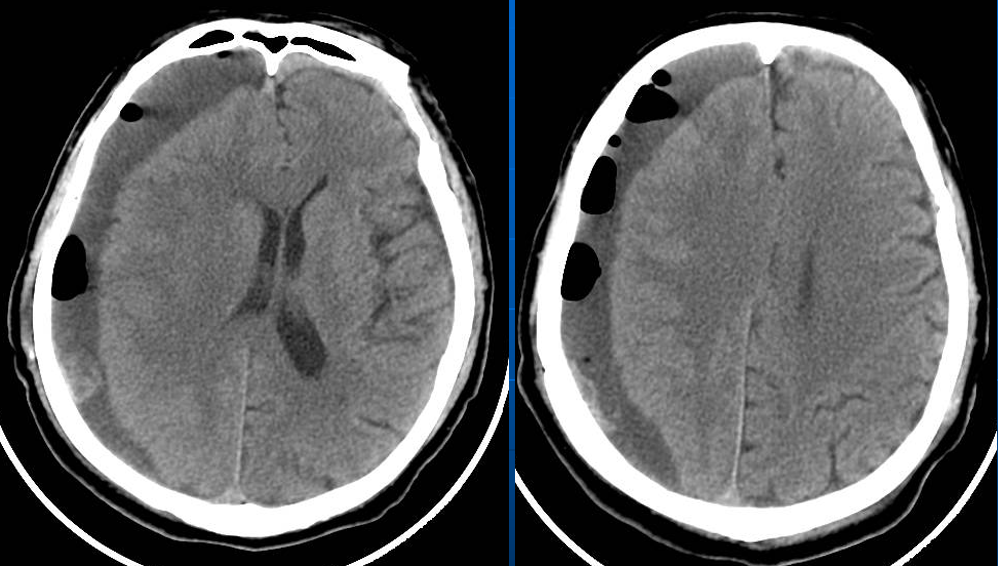

患者约2个月前无明显诱因(否认外伤史)间断出现头痛,头痛为胀痛,左侧较明显,恶心未吐,食欲、睡眠尚可,未予特殊诊治,1个月前患者头痛逐渐加重,思睡,反应略迟钝,行头部CT检查示“慢性硬膜下血肿(双侧)”,于2018年12月15日行颅骨钻孔引流术(左)。术后9天患者恢复良好出院。出院后2周于2019年1月9日患者头痛再次加重,伴有反应迟钝,走路困难,疲乏无力再次就诊,头部CT示“慢性硬膜下血肿(右侧)”,当日再次行颅骨钻孔引流术(右)。术后患者一般状态逐渐好转,无抽搐,无尿便失禁。

术后情况

术后当日(2019年1月16日)

术后3天(2019年1月18日)

老年患者容易出现原硬膜下血肿排空后被硬膜下积液取代现象, 这与老年患者有脑萎缩, 脑组织膨起不良有关; 有肝、肾功能不全或凝血机制不良者容易术后硬膜下再出血。

血肿复发出现明显症状最早是术后30小时, 晚者是在术后1个月, 这可能与慢性硬膜下血肿患者血肿排空后颅腔内有较大的代偿空间和包膜内再出血渗出较为缓慢有关, 术后应按时复查颅脑CT。

对于老年患者出现硬膜下积液, 如果没有颅高压症状, 不必急于行再引流手术, 必要时可使用低压泵行硬膜下腔-腹腔分流术。

高龄脑萎缩。

脑萎缩较明显。

脑组织顺应性差,血肿机化、包膜。

存在分隔。